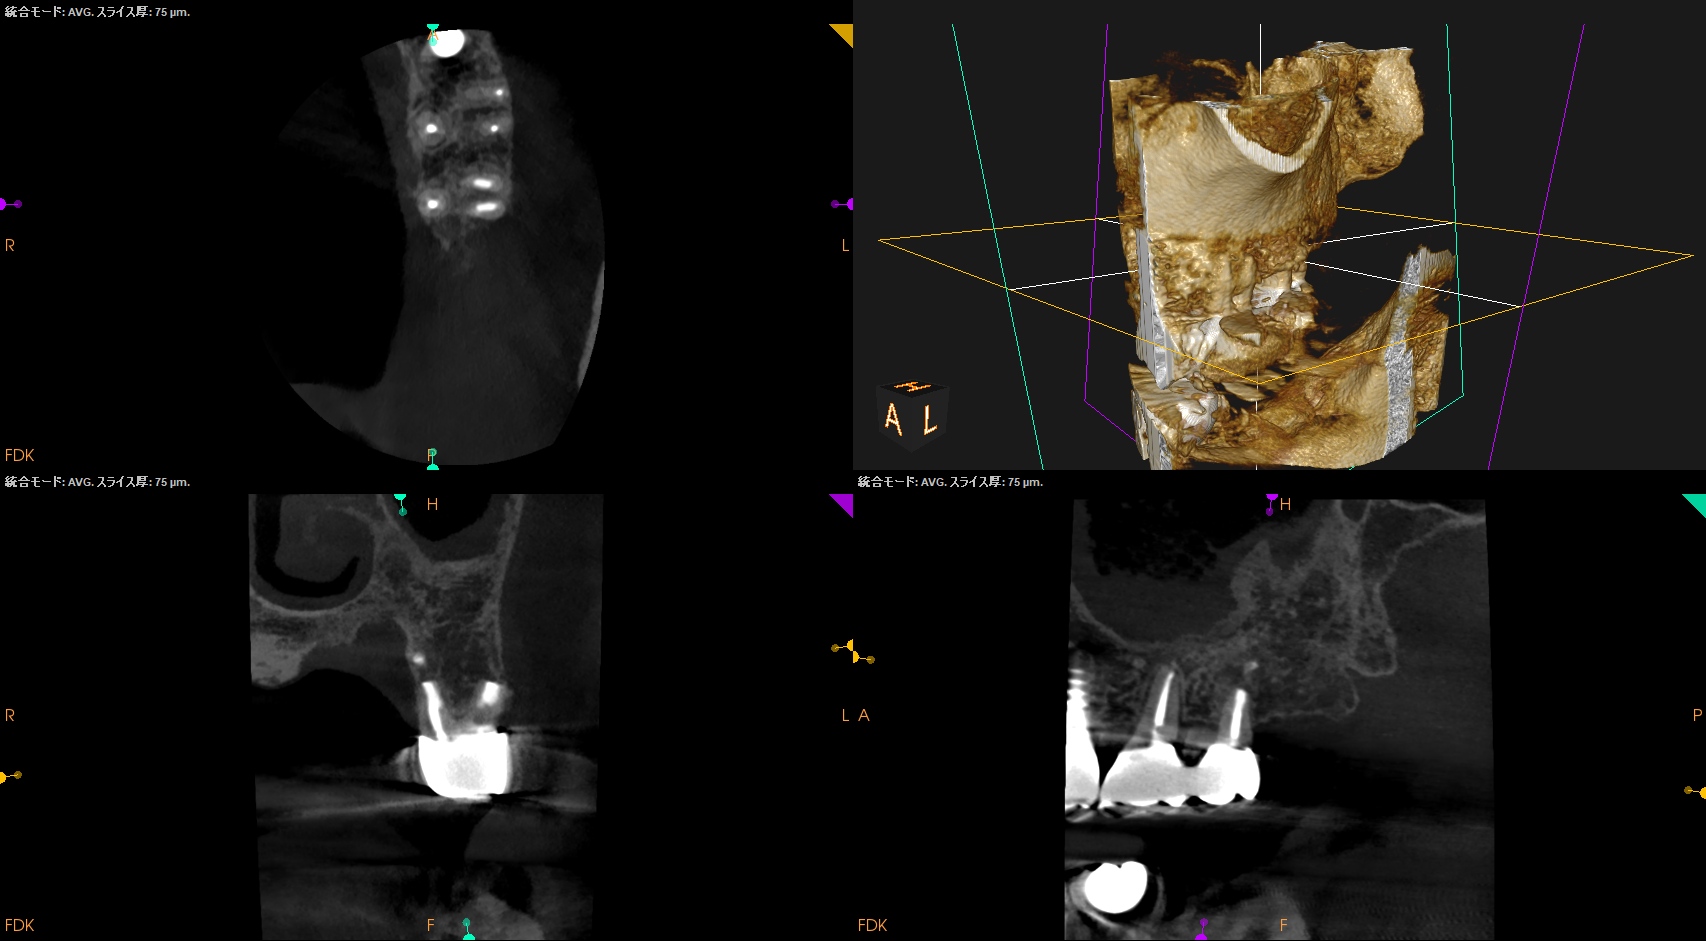

PA, CBCTを撮影した。

DBの破折ファイルは除去できていないが病変は消失している。

CBCTも撮影した。

術前と比較した。

ということで、臨床症状と術前/術直後の骨欠損(根尖病変)も消失し、歯槽骨が回復したため, この日で終診とさせていただいた。